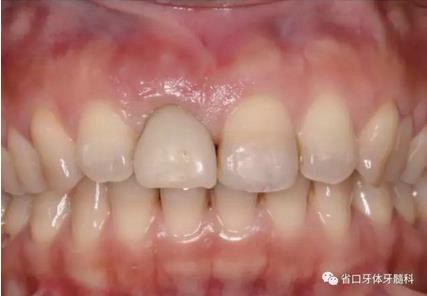

圖1 術(shù)前口內(nèi)照

圖2 術(shù)前口內(nèi)照

圖3 術(shù)前口內(nèi)照

1.?病例簡介 43歲女性患者,主拆:右上前牙松動(dòng)不適數(shù)日要求修復(fù)?,F(xiàn)病史:患者數(shù)年前右上前牙因“齲壞”于外院行根管治療(具體不詳),數(shù)日前牙冠松動(dòng)不適,現(xiàn)覺影響咀嚼及美觀,遂來我院要求進(jìn)一步診治。否認(rèn)高血壓、心臟病等重大疾病,否認(rèn)結(jié)核、肝炎等傳染病史,否認(rèn)手 術(shù)、輸血史等,未發(fā)現(xiàn)藥物過敏。無吸煙習(xí)慣。臨床檢查:口外觀顏面基 本對稱,皮膚無紅腫破潰,顳下頜關(guān)節(jié)區(qū)無彈響、雜音、壓痛,開口度約 37mm,開口型“↓”,頜下、刻下和頸部未及腫大淋巴結(jié)。中位笑線??趦?nèi)檢查,口腔衛(wèi)生可,色素(+),BOP(-),PD=2mm,上頜右側(cè)中切 牙冠部變色,冠根折斷至齦下3mm,叩不適,松動(dòng)Ⅱ°~Ⅲ°。牙齦稍紅, 齦緣水平及齦乳頭高度可,屬于中厚齦生物型,附著齦寬度約5mm,唇系帶附著可。上頜右側(cè)中切牙缺牙間隙與對側(cè)同名牙一致,約>7mm,修復(fù)空 間良好。與對頜牙覆合覆蓋正常。MCT檢查示上頜右側(cè)中切牙冠根折斷至骨 下,根管內(nèi)見充填物,根充不全,根尖見陰影,大小約3mm×3mm。牙槽窩根方可用骨量可,唇側(cè)骨壁完整,冠方骨壁厚度約1mm。